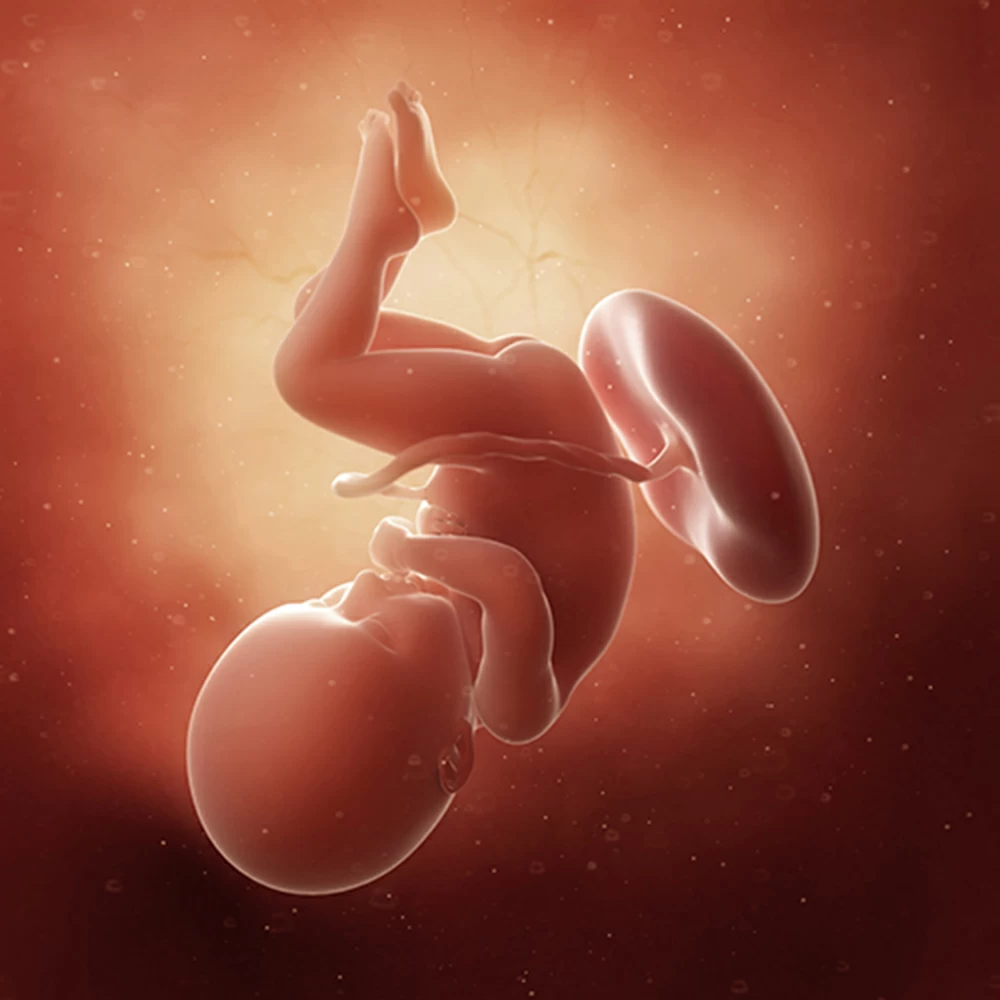

Неделя № 32

Рост ребенка составляет около 42 см, вес – 1700-1800 грамм.

Плод вырабатывает специальный гормон, который способствует образованию в организме матери эстрогена, в результате молочные железы начинают готовиться к выработке молока.